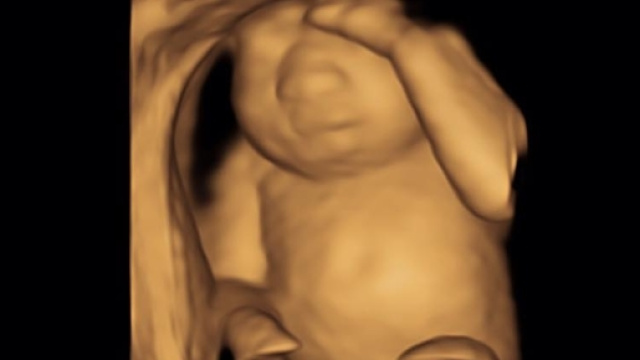

È il 13 dicembre quando Keri, postando su Facebook l’immagine dell’ecografia della sua bambina, decide di condividere il dolore pubblicamente e racconta: "Questo è il cuore perfetto di nostra figlia.

Ha dei piedi perfetti e mani perfette. Lei è perfetta, reni, polmoni e fegato perfetti. Purtroppo, non ha un cervello perfetto. Abbiamo scoperto recentemente che è affetta da anencefalia ed è terminale. Di fronte alla terribile opzione di interrompere la gravidanza, abbiamo deciso di portarla a termine, così Eva, che significa letteralmente vita, potrà crescere forte e dare vita a più persone attraverso la donazione dei suoi organi. Non è stata una decisione facile. Per le prossime 20 settimane sentirò i suoi calci, il singhiozzo e saremo in grado di sentire il suo cuore perfetto battere, sapendo che staremo con lei solo poche ore quando nascerà. Come potete immaginare, siamo devastati, ma abbiamo un fantastico supporto dalla nostra famiglia, gli amici, la parrocchia e i dottori.